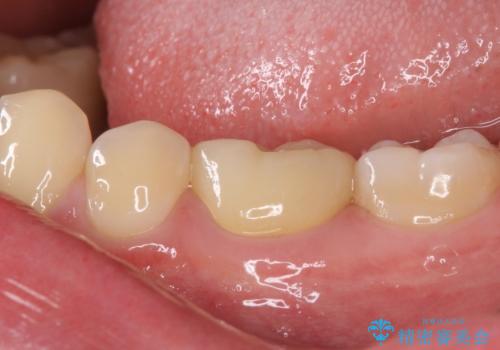

虫歯除去後に痛みは収まり、神経も保存することができました。

変色していた歯もセラミッククラウンで自然な色合いとなり、患者様には大変満足していただきました。